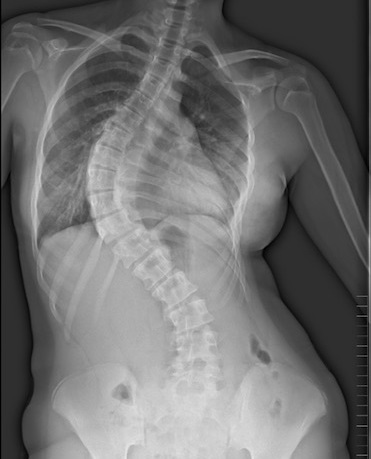

Per una sperimentazione sulla scoliosi idiopatica adolescenziale presso il Dipartimento Rizzoli-Sicilia

8 Giugno 2022L’Istituto Ortopedico Rizzoli ha in corso una sperimentazione rivolta ad adolescenti con scoliosi idiopatica (11-17 anni) e a volontari in buona salute (11-17 anni).

Lo studio ha l’obiettivo di identificare e caratterizzare delle particolari molecole presenti nel sangue per la diagnosi e la valutazione della progressione della patologia.